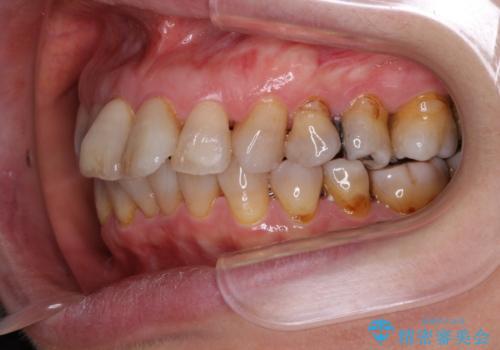

- 口元の突出感と歯の色を気にして来院された患者様です。

口元を引っ込めるために上下左右第一小臼歯4本を抜歯し、ワイヤー矯正を行うこととしました。

歯の色はホワイトニングかセラミッククラウンで対応することとしましたが、ブラックトライアングルが目立つことが予想されたため、目立つ範囲をオールセラミッククラウンで補綴することとしました。